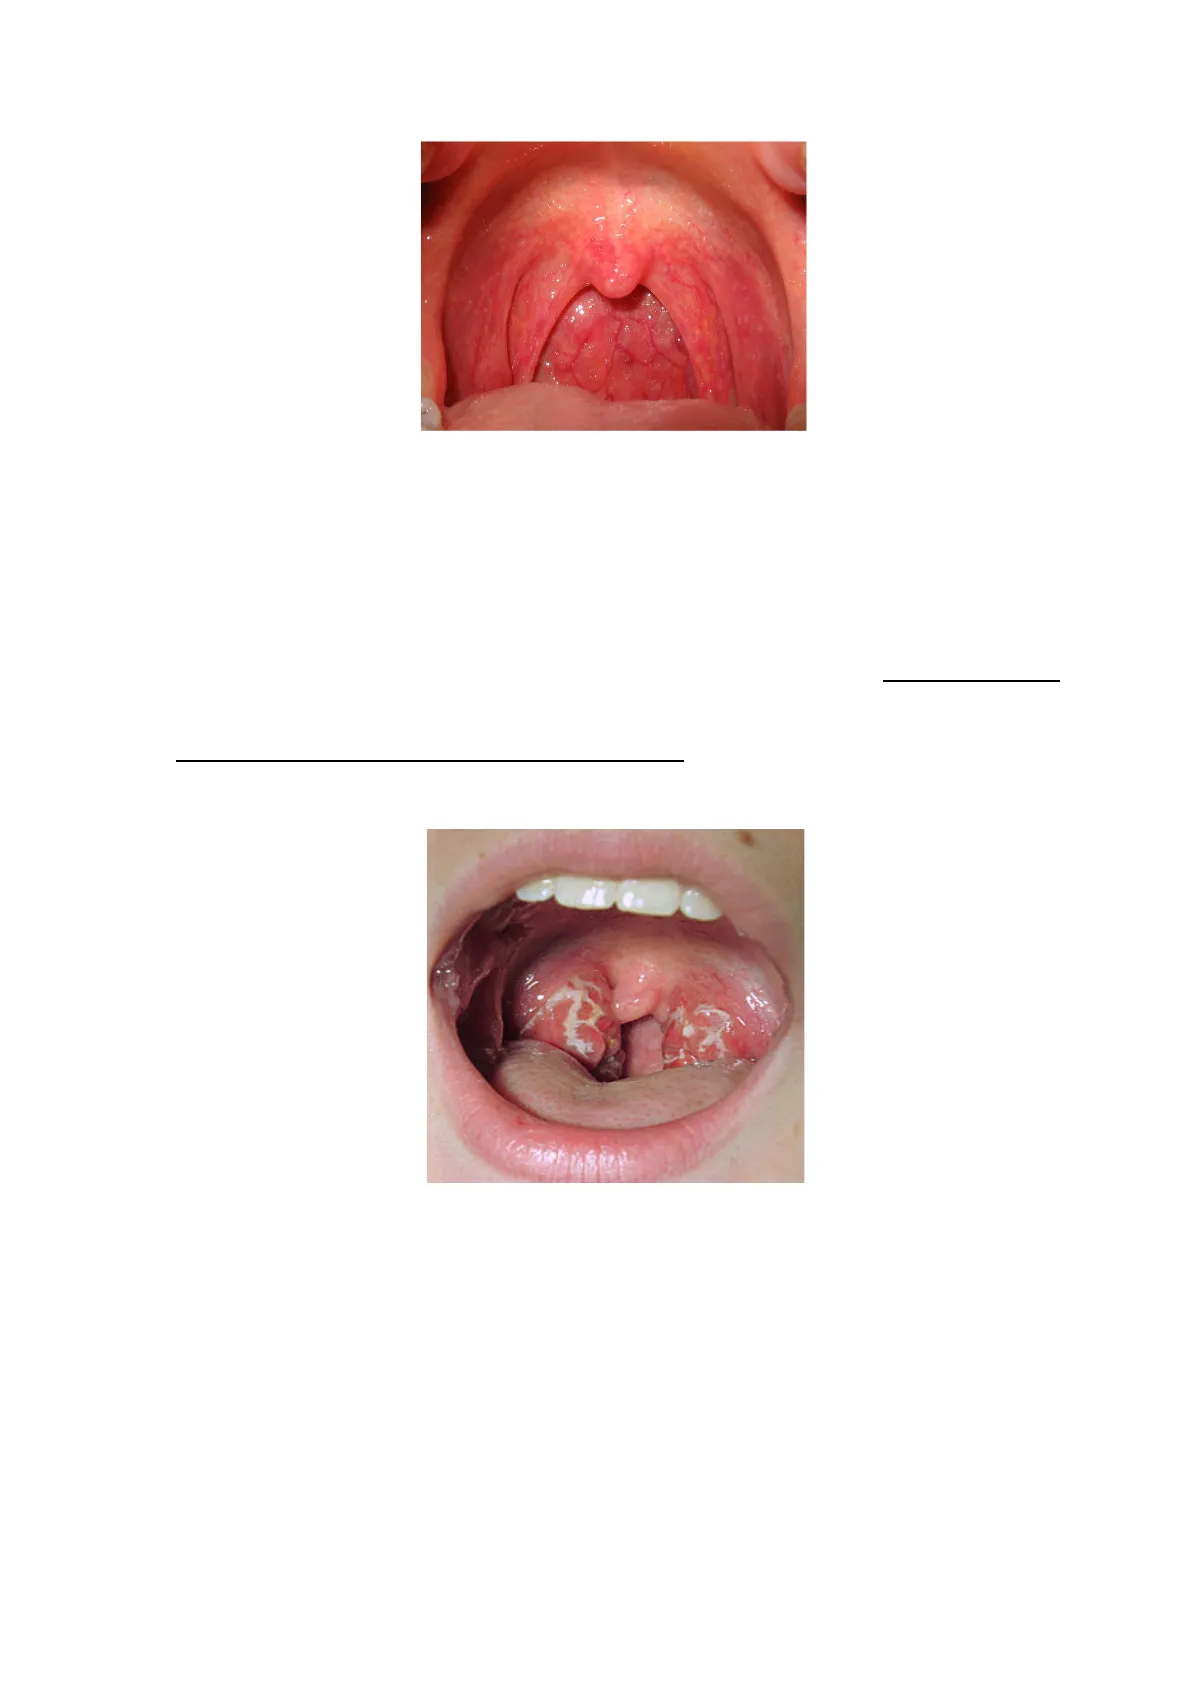

! Di"norma"nell’orofaringe"sono"presenti,"variamente"distribuiti,"popolazioni"di"streptococchi"

emolitici"(S.+mutans+e+S.+salivarius),"alcune"specie"del"genere"Neisseria"(non"la"

gonorrhoeae),"stafilococchi"coagulasi"negativi,"lo"Streptococco+pneumoniae,"

! l’Haemophilus+hemolyticus,"

+++alcune"Enterobatteriacee,+e"occasionalmente"streptococchi"beta+emolitici"non"appartenenti"al"

gruppo+A.++"

La"ricerca"del"patogeno"principale"sui"tamponi"faringei"è":"

lo"Streptococco+beta+emolitico+di+gruppo+A+("vedi"immagine"successiva)"

• Di norma nell'orofaringe sono presenti, variamente distribuiti, popolazioni di streptococchi emolitici (S. mutans e S. salivarius), alcune specie del genere Neisseria (non la gonorrhoeae), stafilococchi coagulasi negativi, lo Streptococco pneumoniae,

• l'Haemophilus hemolyticus, alcune Enterobatteriacee, e occasionalmente streptococchi beta emolitici non appartenenti al gruppo A.

La ricerca del patogeno principale sui tamponi faringei è : lo Streptococco beta emolitico di gruppo A ( vedi immagine successiva)